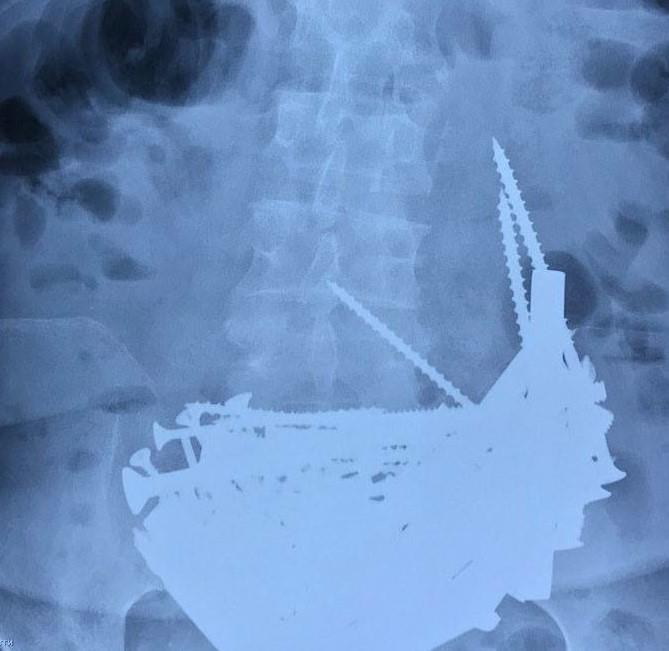

Doktorka Irina Goliševa utvrdila je da su grlo i jednjak pacijentkinje u idealnom stanju, ali zatim je endoskop otkrio neočekivani sadržaj želuca: u njemu se nalazila ogromna količina stranih tela. Posle detaljnog pregleda doktorka je utvrdila da se radi o ekserima i šrafovima. Pokušala je pomoću endoskopa da ih izvadi, ali je uspela da izvuče samo četiri eksera. Nije želela ženu da izlaže daljem riziku i hitno je pozvala hirurge radi konsultacija.

Oni su preporučili hitnu operaciju pod totalnom anestezijom. Među uklonjenim stranim telima bili su dugački ekseri, veliki šrafovi, matice, reze za vrata, delovi armature dugi do 15 centimetara, pa čak i srebrni lančić finoće 925. Na kraju su iz želuca izvađena 152 metalna predmeta koji su već počeli da oksiduju, a niko osim same žene nije mogao da kaže koliko dugo su se predmeti tu nalazili. Posle operacije pacijentkinja je smeštena na odeljenje za reanimaciju i trenutno je njeno stanje stabilno.